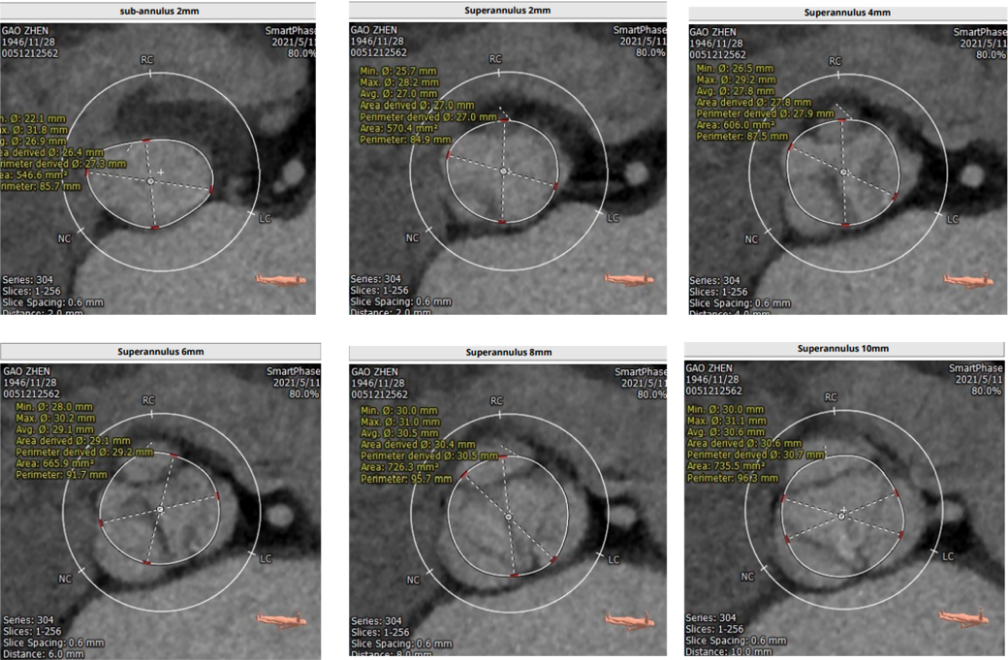

TAVR术前评估及手术过程